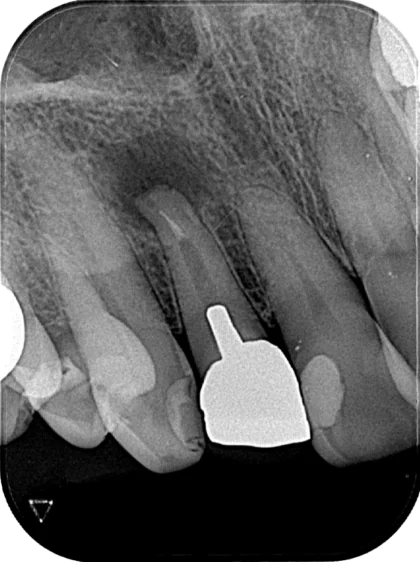

Case01

診断:慢性根尖性歯周炎

Before

After

| 主訴 | 前歯に違和感が前からあって、最近ズキズキしたりしてきた。 |

| 治療内容 | 診査したところ、既根充歯に根管内に細菌が侵入して感染根管となり歯根の先から骨の中に細菌が侵入し免疫反応により歯周炎を起こし、根尖の骨の吸収が起きていると診断。根管治療を開始した。根管内を洗浄、拡大しMTAにて根管充填を行なった。充填後、3ヶ月ほどで痛み、違和感が再発した。根尖外部にも細菌感染が起きている可能性が高いことから、歯根端切除術を行なった。術後3ヶ月で根尖の骨の再生がレントゲンで確認され、治癒傾向にあることが確認できた。 |

| 治療期間 | 初回の根管治療から根管充填 2回 その後、3ヶ月後に歯根端切除術 |

| リスク | 既根充歯の再治療のため、処置時に歯根破折のリスクがある。 歯根端切除後も細かい部分に感染が残っている場合、免疫反応により炎症が再発するリスクがある。 |

| 治療後の経過 | 歯根端切除後は、違和感が消失し日常生活に支障がなくなった。 術後3ヶ月で骨膿で溶けていた骨が再生され、普通に違和感なく食事ができるようになった、とのこと。 |

| 費用 |

・初診料:15,000円 計:318,000円 |